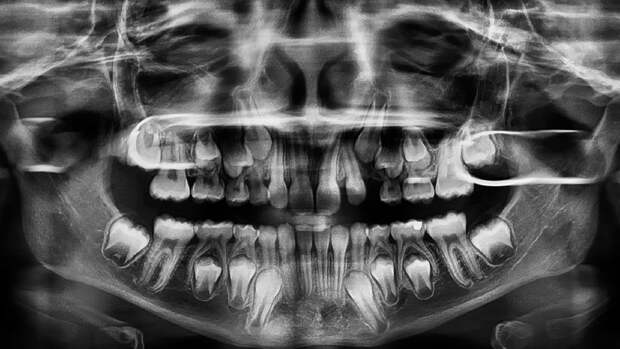

Работа была опубликована в журнале Scientific Reports.Корень и шейку зуба человека покрывает особая костная ткань - цемент. Она на треть состоит из органических веществ и служит для плотного закрепления зуба в зубной лунке. На протяжении жизни, почти как годовые кольца у деревьев, образуются новые слои цемента. Они и привлекли внимание ученых.

С помощью поляризационной световой микроскопии исследователи рассмотрели 47 зубов от 15 людей, которые жили в наше время, но уже умерли. Возраст людей составил 25-69 лет. От их родных ученые получили информацию об истории болезни каждого человека, образе его жизни, важных событиях - например, переезде из города в сельскую местность, и прочие данные.

Изучая слои цемента на зубах, ученые обнаружили заметные изменения микроструктуры, которые по времени появления совпадали с теми или иными важными жизненными изменениями.